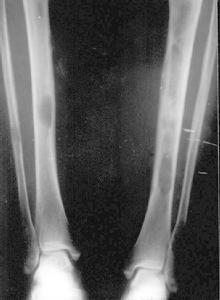

MAS的骨組織被異常增生的纖維組織所取代,表現為不同程度的骨膨脹,骨皮質變薄,但完整。骨密度可為均勻性減低,或呈磨玻璃樣,或見條索狀、斑點緻密陰影。國內總結X線分4型:

(1)囊狀改變:分單囊和多囊,邊緣硬化,囊內常見條狀骨及斑點狀緻密影,常見於管狀骨和肋骨。

(2)毛玻璃改變:髓腔囊狀膨脹呈毛玻璃狀密度,內可有條狀骨紋和斑點狀鈣化。

(3)絲瓜筋狀改變:骨小梁粗大扭曲,頗似絲瓜筋狀,嚴重者如蛛網狀,長管狀骨粗大,骨狀紋一般和縱軸平行。

(4)蟲蝕狀改變:單發或多發的溶骨性改變,邊緣銳利如蟲蝕樣,可類似溶骨性轉移性破壞。

此外,脊柱和長骨常伴病理性骨折。